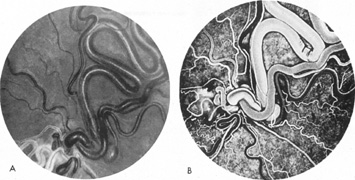

Vertebrobasilar System

Tortuous or redundant basilar arteries are not uncommon in the older age group. Occasionally, gross dilation or ectasia develops so that the basilar artery acts as a mass in the posterior fossa. This phenomenon produces signs of low-pressure hydrocephalus, cranial nerve palsies, and long tract and sensory signs and may even simulate a cerebellopontine angle tumor or tumor at the foramen magnum.58 It is possible to diagnose such lesions with CT59 or MRI60 but angiography is definitive (Fig. 6). The association of insidious multiple cranial nerve palsies and long tract signs referable to a brainstem level, in an elderly patient with evidence of atherosclerosis, should make fusiform basilar artery dilation a diagnostic consideration.

Fig. 6. Fusiform basilar dilation. A: Lateral projection vertebral arteriogram showing a widened basilar artery (arrow) projecting beyond level of dorsum sellae. B: Anteroposterior projection showing a widened and tortuous basilar artery.

As opposed to saccular basilar aneurysms, fusiform aneurysms tend to occur in the older age group (older than 60 years) and are found predominately in men.2,36 They are commonly associated with hypertension and atherosclerotic cardiovascular disease, and a notable association with abdominal aortic aneurysms also exists.